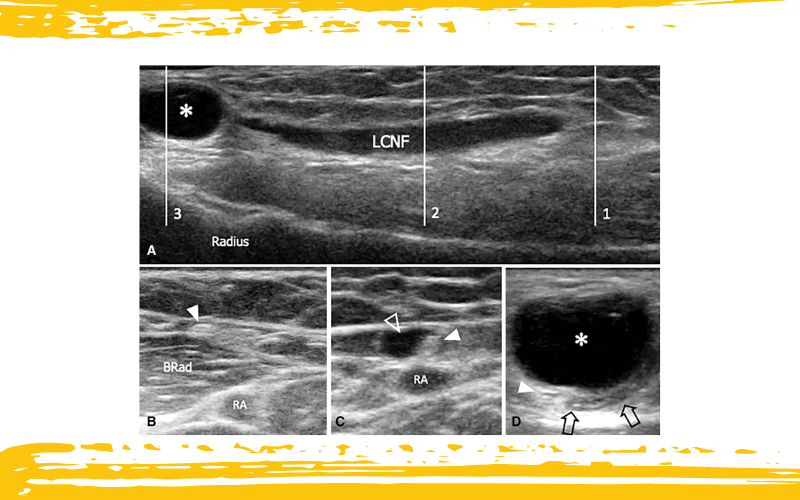

En la imagen A, la ecografía obtenida a nivel de la muñeca en un paciente con aparición reciente de una masa muestra un quiste sinovial ventral de muñeca (asterisco) que penetra en una rama distal del nervio cutáneo lateral del antebrazo (LCNF). El nervio aparece relleno de líquido a lo largo de un tramo extenso.

En la imagen B, el corte ecográfico en la posición 1 (indicada en la imagen A) muestra el LCNF normal (punta de flecha blanca) situado superficial al músculo braquiorradial (BRad).

La imagen C corresponde al corte en la posición 2 (desde la imagen A), donde la lesión quística (flecha delineada) se observa invadiendo el epineurio del LCNF y desplazando radialmente los fascículos nerviosos (punta de flecha blanca).

En la imagen D, correspondiente a la posición 3 de la imagen A, el quiste sinovial (asterisco blanco), con presión adicional aplicada por el transductor, comprime la arteria radial (flecha delineada) en su superficie inferior. Los fascículos del LCNF (punta de flecha blanca) se observan profundos al quiste.

RA: arteria radial.